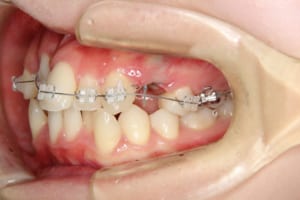

治療中

治療内容 唇側矯正装置を使用した成人矯正治療を行いました。

使用した装置 マルチブラケット装置(唇側矯正)

InVuブラケット

シルバーワイヤー

ホールディングアーチ

歯科矯正用アンカースクリュー(1本)

その他/備考 上顎右側中切歯および側切歯が、埋伏していた犬歯によって歯根吸収していました。

牽引に半年かかりました。

顎間ゴムも頑張ってくれたが期間がかかりました。